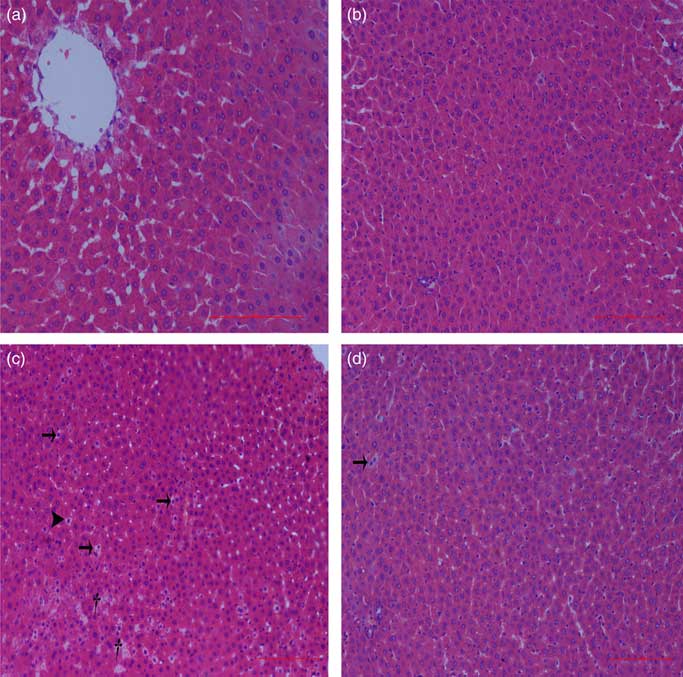

Liver histological changes

Normal histologic structures were observed in the liver of NBW and NC rats (Fig. 4(a) and (b)). In the liver sections of IUGR rats, vacuolisation and cell oedema were prevalent in the hepatocytes, and fat cells showed signs of mild denaturation (Fig. 4(c)). In the IC group, vacuolisation was significantly reduced and no fat cells were observed (Fig. 4(d)).

Fig. 4 Light microscopy of liver tissue in different groups (200× magnification): (a) normal birth weight rats, (b) normal birth weight rats supplemented with curcumin, (c) intra-uterine growth retardation rats and (d) intra-uterine growth retardation rats supplemented with curcumin. Haematoxylin–eosin, scale bar=100 μm. † Vacuole; ![]() , fat cell;

, fat cell; ![]() , cellular oedema.

, cellular oedema.

IUGR neonates are associated with a high risk of inflammation and oxidative stress( Reference Tarryadkins, Fernandeztwinn and Hargreaves 28 ). TNF-α is a key immune modulator, which can activate chemotactic cytokines and produce free radicals, leading to oxidative stress( Reference Starke, Daniel and Dumont 32 ). Furthermore, TNF-α, IL-1β and IL-6 have been implicated as prototype pro-inflammatory cytokines in the pathogenesis of sepsis( Reference Deventer 33 ). Higher TNF-α, IL-1β and IL-6 levels were observed in the serum of IUGR rats, which implied that pro-inflammation occurred in the body. Reports had demonstrated that a strong pro-inflammatory bias existed in IUGR with placental insufficiency( Reference Raghupathy, Al-Azemi and Azizieh 8 ). Significantly high concentrations of TNF-α, IL-1β and IL-6 in IUGR rats were significantly decreased after dietary curcumin supplementation, suggesting that curcumin could reduce inflammatory responses in the serum. These results are similar to those of previous studies in cells( Reference Liu, Shang and Li 34 ) and rats( Reference Soetikno, Sari and Veeraveedu 35 ). The liver is an important organ, and liver dysfunction has been observed in IUGR newborn pigs( Reference Junjun, Lixiang and Defa 7 ). The activities of AST and ALT are positively correlated with portal flow( Reference Kuo, Li and Alfrey 36 ). Hepatic ALT is usually located in the cytoplasm, whereas AST is distributed in the cytoplasm and mitochondrial fractions. However, when the structure of the liver is seriously damaged, ALT and AST are released into the circulatory system, resulting in the improvement of ALT and AST activity in the serum( Reference Nyblom, Berggren and Balldin 37 ). In this study, the activities of serum AST and ALT in the IUGR group were higher than those in the NBW group. The increased activities of serum ALT and AST are generally accepted biomarkers for hepatic dysfunction( Reference Tang, Chao and Xing 38 ). The vacuolisation and cell oedema from the histological examination of liver sections were prevalent in hepatocytes of IUGR rats, which revealed histological damage in the liver of IUGR rats. Meanwhile, fat cells also had mild denaturation. Similar to our findings, IUGR fetuses had a higher activity of glutamate oxaloacetate transaminase and impaired liver function than the normal ones( Reference Liu, Lin and Wang 39 ). After curcumin supplementation, the abnormal levels of serum AST and ALT and liver histological damage improved, and these results were not different from those observed in the normal condition. Previous studies had shown that curcumin could significantly reduce the levels of serum AST and ALT( Reference Zhao, Song and Chai 40 ) and liver injury in mice( Reference Zhang, Xu and Zhang 16 ) and rats( Reference Toydemir, Kanter and Erboga 22 ). Our findings indicated that diets supplemented with curcumin attenuated liver injury and inflammation in IUGR rats. Thus, we concluded that the protective effects of curcumin on the liver may be very important in IUGR rats. To investigate the immunomodulatory mechanisms of curcumin, we detected the expressions of the NF-κB and JAK/STAT pathways in the liver. NF-κB is found in cytoplasm bound to IκB. In response to various stimuli, including cytokines, stress and bacterial pathogens, the latent cytoplasmic NF-κB/IκB complex is activated by phosphorylation( Reference Hiscott, Kwon and Genin 41 ). Phosphorylation of IκB induces their ubiquitination, proteosome degradation and, subsequently, NF-κB release and nucleus translocation( Reference Echeverri, Nancy and Mockus 42 ). NF-κB is one of the most ubiquitous eukaryotic transcription factors that regulate the expression of genes associated with control of inflammatory responses, cellular proliferation/growth, cell adhesion and other processes( Reference Chen, Castranova and Shi 43 ). Our results showed that IUGR induced increased levels of phosphorylated IκBα and nuclear NF-κB and decreased levels of cytoplasmic phosphorylated NF-κB in the liver. Similar to our study, Zhong et al.( Reference Zhong, Li and Huang 44 ) also reported that the IκB was activated and the expression of NF-κB was increased by IUGR. These results suggested that the activation of the NF-κB/IκB complex might be related to increased levels of cytokines in IUGR, including TNF-α and IL-1β. The JAK2/STAT3 pathway is known to be involved in the immune response of numerous cytokines, including IL-6, and activated in response to injury( Reference Yang, He and Hao 45 ). Our results demonstrated that IUGR induced high levels of phosphorylated JAK2 and STAT3 in the liver. The activation of the JAK/STAT3 pathway might be the result of increased IL-6 in IUGR rats. Our results also showed that expression levels of Tnfa, Il1b and Il6 were up-regulated in the liver of IUGR rats. Importantly, dietary curcumin supplementation obviously inhibited the phosphorylation levels of the NF-κB pathway and JAK2 in IUGR rats and down-regulated the expression of those downstream genes. These observations supported that curcumin attenuated inflammation through the NF-κB( Reference Soetikno, Sari and Veeraveedu 35 , Reference Surh, Chun and Cha 46 ) and JAK/STAT pathways( Reference Kim, Park and Joe 47 ) in the liver of IUGR rats, which resulted in the negative regulation of cytokines (TNF-α) and pro-inflammatory interleukins (IL-1β and IL-6)( Reference Reyes-Gordillo, Segovia and Shibayama 48 ).